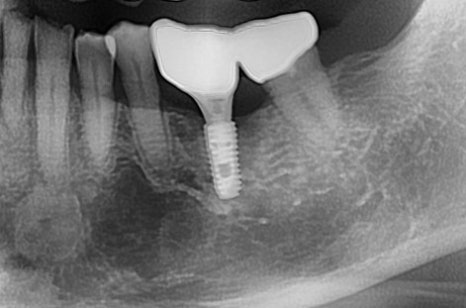

이번 케이스는

저희 아버님이십니다.

과거에도 한번 신경치료 부위가 재발이 돼서

재신경치료 후 보철을 해드렸었는데

거의 10년이 넘어 이번에는

뿌리 쪽 염증과 치주 염증이 복합적으로 생기셨습니다.

이미 뿌리도 녹고 있는 상황이었기 때문에

안타깝지만 아버님께 발치를 설명드리고

대신 염증으로 인해 광범위하게 녹아있는 치조골 주변에

골 이식술을 튼튼하게 하고 임플란트를 완성 시켜드렸습니다^^